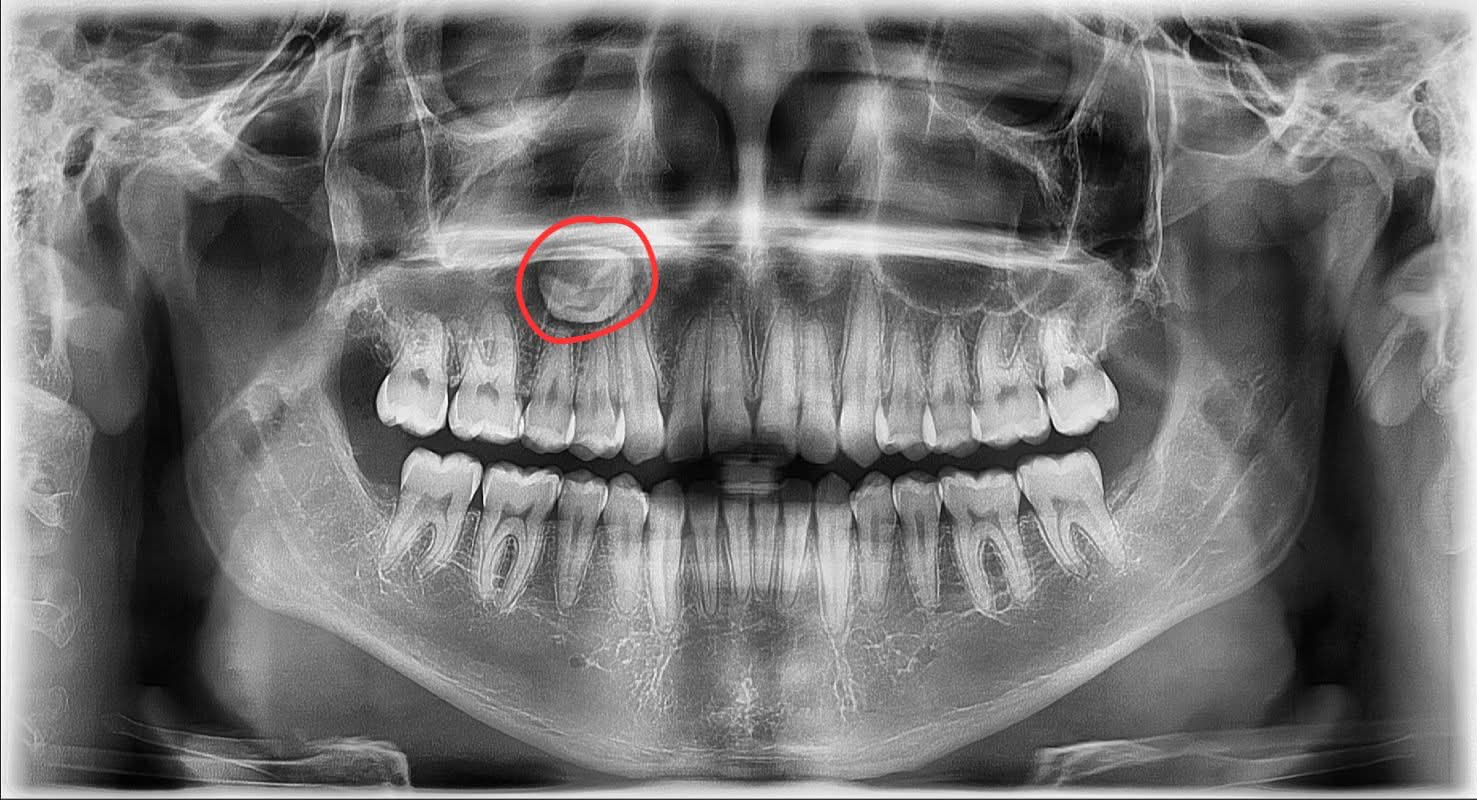

ANTES · 16 AÑOS

Radiografía panorámica a los 16 años mostrando cordal impactada

Imagen izquierda (16 años): Un paciente adolescente acude a un odontólogo general para extraer su cordal inferior. El círculo rojo señala la pieza antes del intento de extracción.